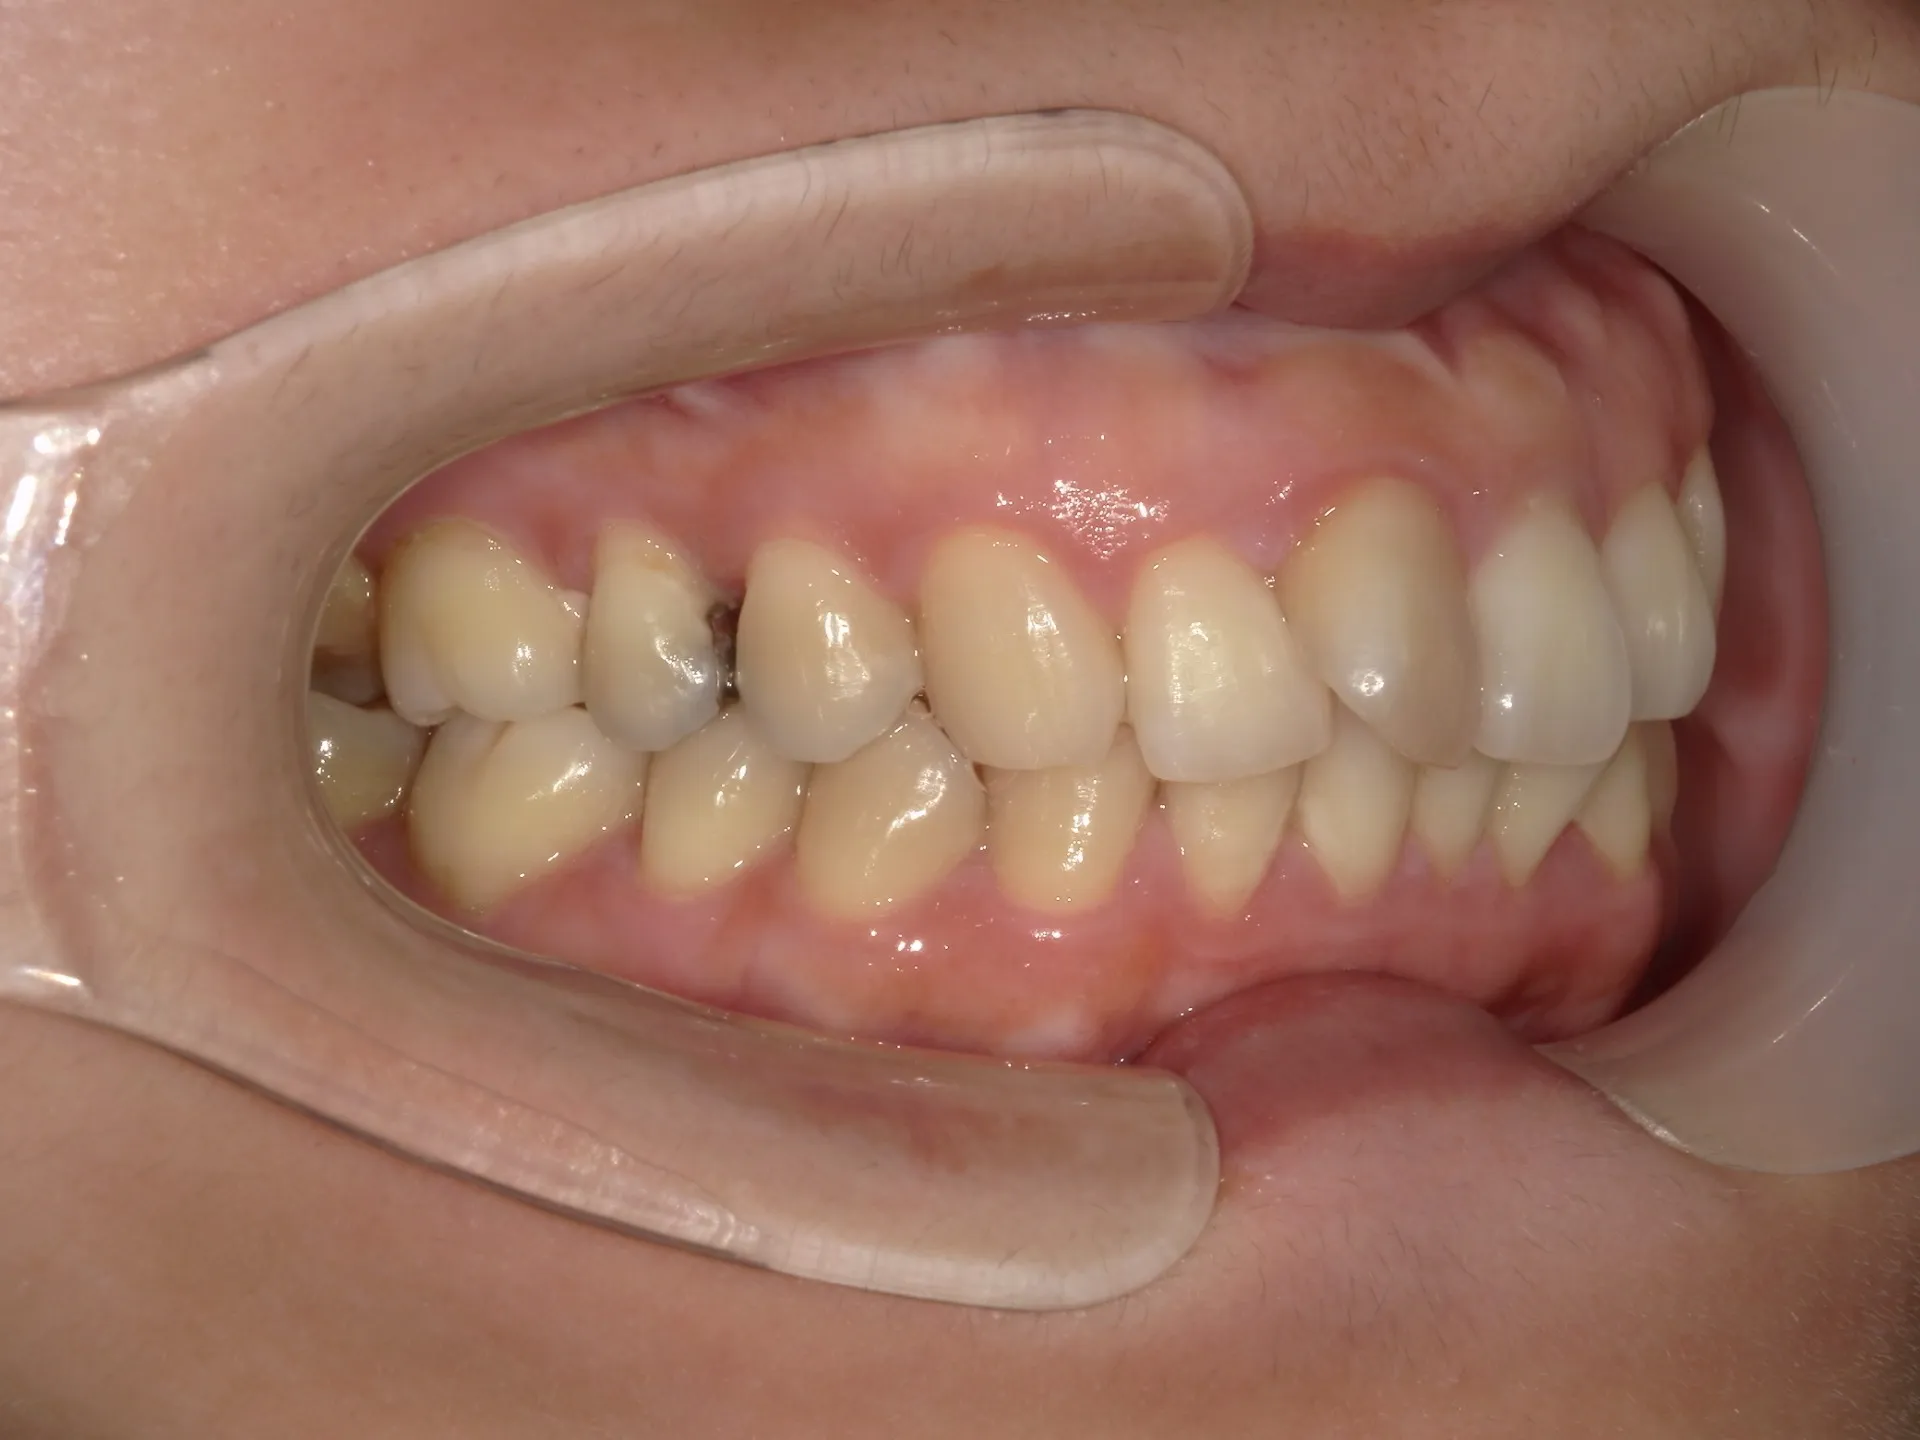

今回はねじれてしまった前歯の矯正治療をインビザラインというマウスピース矯正で治療した症例をご紹介いたします。